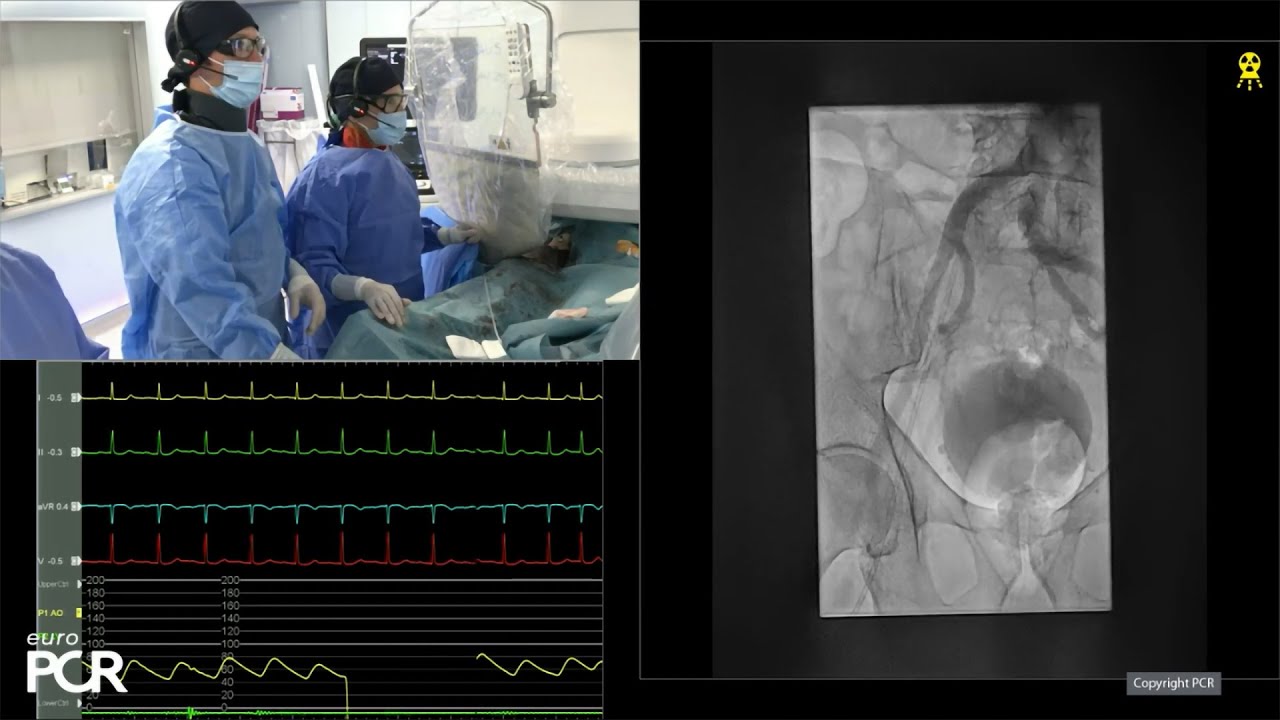

CT scan analysis in live case at EuroPCR 2024